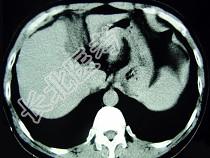

- 单项选择题男,52岁, 中上腹痛,影像检查如图, 最可能的诊断是  (    )

- A、慢性肥厚性胃炎

- B、胃癌

- C、胃溃疡

- D、胃平滑肌瘤

- E、胃平滑肌肉瘤